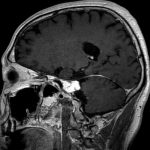

断層撮影

手術前1

手術前2